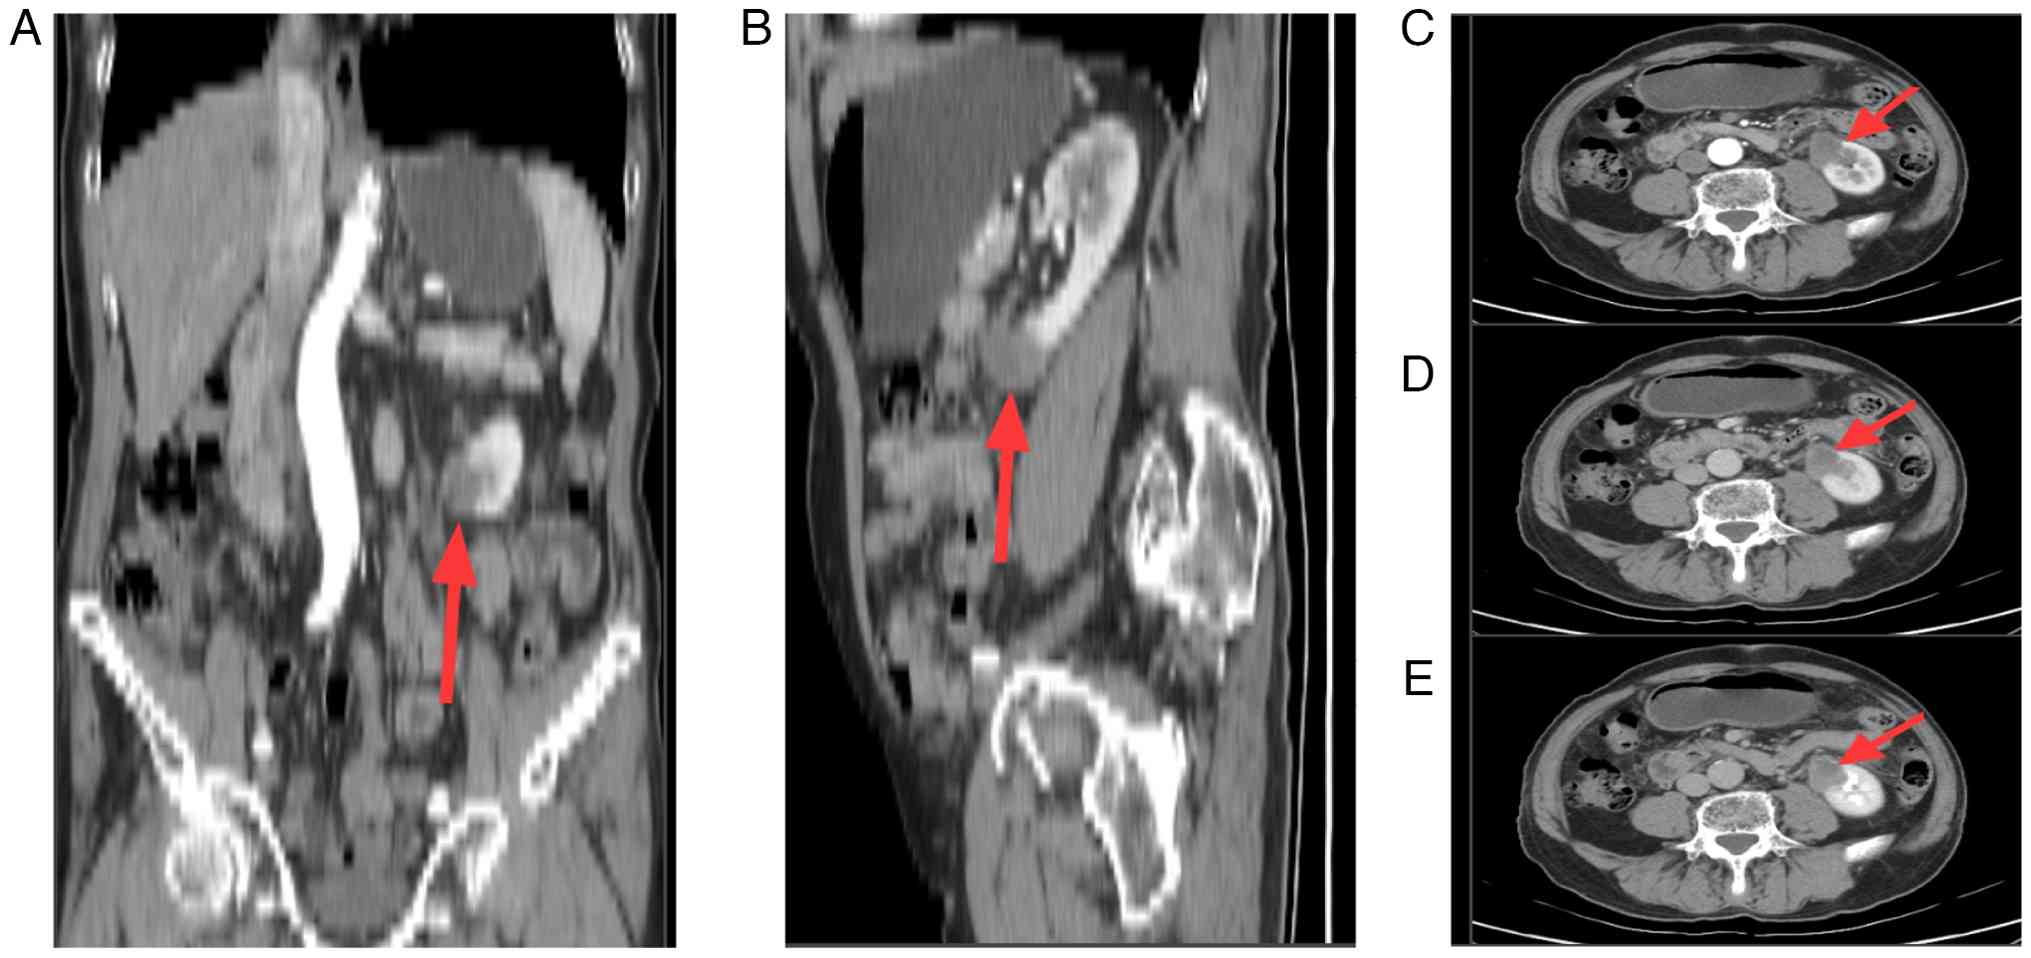

After a disease-free interval of ~9 months, enhanced abdominal CT scans revealed a round isodense lesion in the lower pole of the left kidney, mostly protruding beyond the renal contour, measuring ~2.5×3.0×2.6 cm, with progressive enhancement on the contrast scan (Fig. 4). Enhanced chest CT and enhanced brain MRI scans did not reveal any further metastases. Bone scans were negative. The patient was asymptomatic, without abdominal discomfort, hematuria or other urinary system symptoms. It was difficult to distinguish between incidental renal cell carcinoma and renal metastasis based on imaging alone, and the patient refused a biopsy of the renal lesions. Therefore, after multidisciplinary discussion, in a meeting involving urologic oncologists, medical oncologists, radiologists and pathologists, surgical treatment was recommended.

Results of preoperative abdominal

contrast-enhanced CT. Abdominal contrast-enhanced CT showed a

2.5×3.0×2.6-cm tumor in the lower pole of the left kidney. (A)

Coronal view. (B) Sagittal view (red arrow) revealed a

well-encapsulated mass in the left kidney. (C) Contrast-enhanced CT

scans showed mild enhancement that was less than that for the

cortex in the cortical phase (62 HU). (D) The attenuation of the

tumor (80 HU) was slightly increased (red arrow) in the medullary

phase. (E) In the delayed phase, the attenuation of the tumor

decreased to 75 HU (red arrow). CT, computed tomography.

Figure 4.

Results of preoperative abdominal contrast-enhanced CT. Abdominal contrast-enhanced CT showed a 2.5×3.0×2.6-cm tumor in the lower pole of the left kidney. (A) Coronal view. (B) Sagittal view (red arrow) revealed a well-encapsulated mass in the left kidney. (C) Contrast-enhanced CT scans showed mild enhancement that was less than that for the cortex in the cortical phase (62 HU). (D) The attenuation of the tumor (80 HU) was slightly increased (red arrow) in the medullary phase. (E) In the delayed phase, the attenuation of the tumor decreased to 75 HU (red arrow). CT, computed tomography.